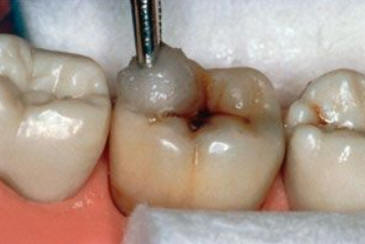

Una morfología de la fisura estrecha, con forma de botella de "Coca-Cola" genera un nicho ecológico ideal para la colonización de cualquier bacteria productora de ácidos. Al no poder remover en forma períodica dicho biofilm de una zona tan estrecha, el ataque ácido genera una lesión cariosa en la dentina, con un aspecto de esmalte intacto a la inspección visual, o sea un típico código 3 y 4 de ICDAS Completo. (Caries Moderada para el ICDAS COMBINADO)

Imagen digital que representa la microfiltración y penetración del sellante realizado.

Microfotografía: Muestra como el sellador obtura la caries subyascente, evitando su avance.

Código 3 (Caries moderada) in vitro. Los códigos 3 in vivo debe ser sellado para evitar el avance del proceso carioso. (MNO)

Código 4 (Caries moderada) in vitro. Los códigos 4 in vivo deben ser tratados en forma operatoria con preservación dental (MOPD), porque presentan dentina infectada.